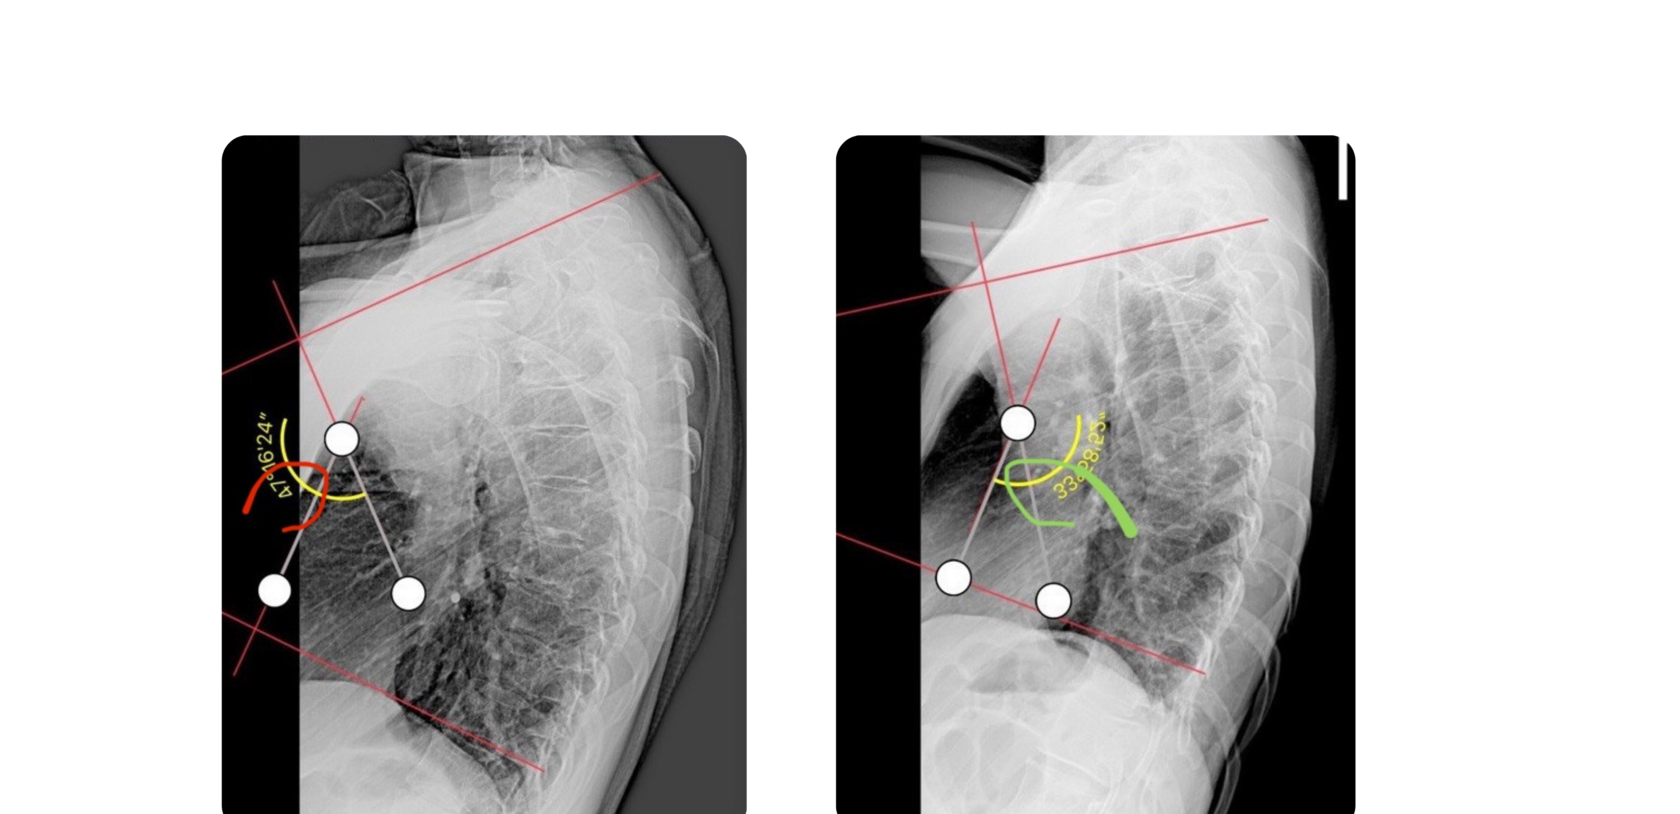

ДЗ: рентген-снимки и заключения "ДО"

ДЗ: рентген-снимки и заключения "ПОСЛЕ"